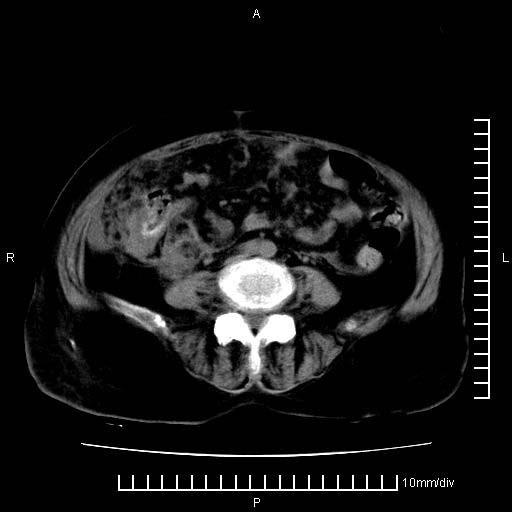

上腹疼痛月余,外院核磁诊断胰腺癌。现临床示右下腹可明显触及包块,可片子上怎么没有看到?

1.胰腺颈体部癌。

2。腹腔积液。

3。右胸腔积液,伴右肺下叶部分萎陷。

4。右肾盂囊肿。

胰腺体部癌累及周围器官,腹膜、粘连

1。胰腺ca伴腹膜腔转移

2。肝左叶低密度灶,考虑转移可能

胰腺体部癌累及周围器官,腹膜、粘连,临床摸到的可能是粘的组织

胰腺结构模糊,胰尾部见囊性包块,周围脂肪密度增高,左肾前筋膜增厚,胸水、腹水。不符合胰腺ca伴腹膜腔转移。考虑胰腺炎伴假性囊肿形成、胸腹腔积液。

右肾盂囊肿。

1)考虑胰腺癌并胰腺假性囊肿形成。2)肝内低密度灶,不排除转移。3)右肾盂积水。4)腹水。5)右侧胸腔积液并右肺下叶部分膨胀不全。